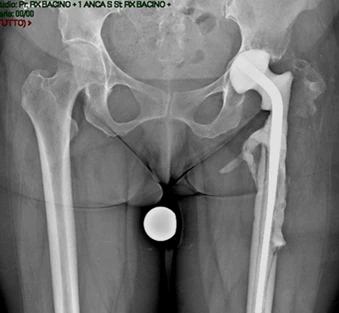

Il Cotile Mpact Ilac Screw viene impiegato quando il normale “alloggio” dell’anca è compromesso da:

- Mobilizzazione della vecchia protesi che ha “scavato” o distrutto parte del bacino.

- Difetti ossei gravi (classificati come Paprosky II o III) e disgiunzione pelvica

- Esiti di traumi complessi o displasie congenite che alterano l’anatomia standard.

Nella chirurgia di revisione, la ricostruzione dell’osso è la sfida principale. Quando l’osso originario è danneggiato o assente a causa dell’osteolisi, il chirurgo deve ricorrere a tecniche avanzate per ripristinare il supporto meccanico e biologico.

In molti casi è necessario l’utilizzo di protesi speciali (da revisione), innesti ossei o sistemi di ricostruzione modulari per sopperire alla perdita di tessuto.